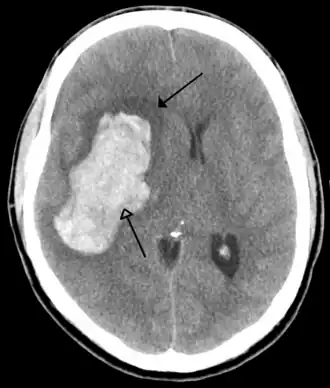

Hersenbloedingen

Hersenbloedingen kennen twee hoofdtypen:[12][13]

- Intracerebrale bloeding, waarbij de bloeding in de hersenen ontstaat, bijvoorbeeld als een ader knapt. Er kan onderscheid gemaakt worden tussen een intraparenchymale bloeding (bloeding in het functionele hersenweefsel) of intraventriculaire bloeding (bloeding in het ventrikelstelsel).

Hersenbloedingen ontstaan als een bloedvat in de hersenen openbarst. Als dit gebeurt krijgen de hersencellen die normaal door dit bloedvat van bloed worden voorzien geen voedingsstoffen en zuurstof meer en sterven af. Het bloed dat uit het bloedvat vloeit duwt het normale hersenweefsel weg. Door de samendrukking van hersenweefsel dat hierdoor kan optreden treedt verdere beschadiging op. Belangrijke oorzaken van hersenbloedingen zijn hoge bloeddruk, afwijkingen van de bloedvaten zoals aneurysmata en AVM's en hersentumoren.